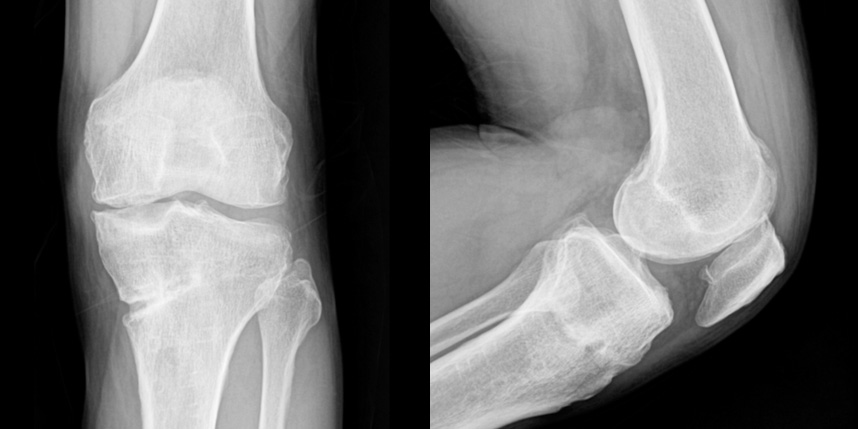

손상된 관절 연골을 재생시켜 관절 기능을 회복하고 통증을 완화하는 치료법입니다.

다양한 연골재생술 기법이 있으며, 환자의 상태와 손상 정도에 따라 적절한 방법을 선택합니다.

외상, 퇴행성 변화, 질환 등으로 인해 관절 연골이 손상된 환자

비수술적 치료로 효과가 없는 환자

젊고 활동적인 환자

관절염 초기 또는 중기 환자